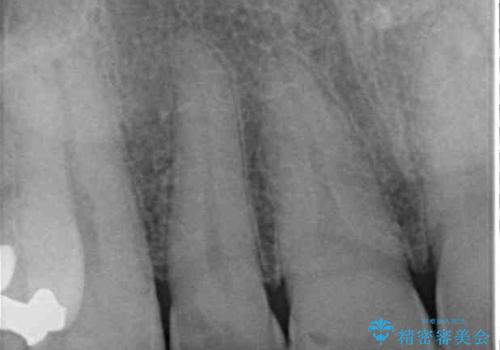

- 内側に倒れている前歯が擦れてしみるとのことで来院された患者様です。

削れていた部分は詰め物が入っていましたが、縁の部分がしみているようで、変色も目立っていたため、オールセラミッククラウンにて補綴治療を行うこととしました。